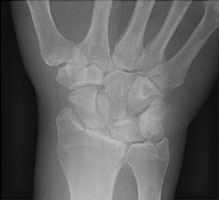

The chauffeur fracture is also called a lorrie or Hutchinson fracture. This fracture results from a direct injury to the thenar side of the wrist, resulting in intraarticular fracture at the base of the radial styloid. This type of fracture resulted from a backfire when a crank was used to start a motor in automobiles.

- Click on the image for a larger versionAPA radiograph of the wrist. There is an intraarticular fracture of the radial styloid.